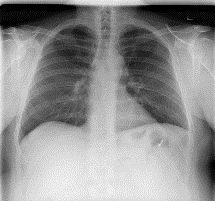

Among various medical imaging tools, chest radiographs are the most important and widely used diagnostic tool for detection of thoracic pathologies. Research is being carried out in order to propose robust automatic diagnostic tool for detection of pathologies from chest radiographs. Artificial Intelligence techniques especially deep learning methodologies have found to be giving promising results in automating the field of medicine. Lot of research has been done for automatic and fast detection of pneumothorax from chest radiographs while proposing several frameworks based on artificial intelligence and machine learning techniques. This study summarizes the existing literature for the automatic detection of pneumothorax from chest x-rays along with describing the available chest radiographs datasets. The comparative analysis of the literature is also provided in terms of goodness. Limitations of the existing literature along with the research gaps is also given for further investigation. The paper provides a brief overview of the present work for pneumothorax detection for helping the researchers in selection of optimal approach for future research.